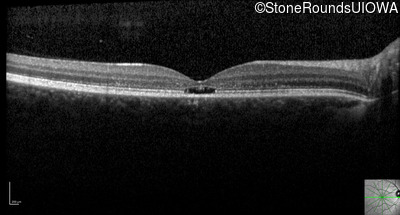

Optical Coherence Tomography - Left - 20/50 -1

Exemplar / OCT Stack

OCT Stack